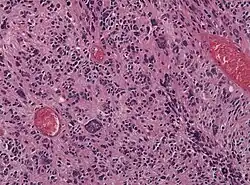

Dysgerminoma | Dysgerminoma characterized by uniform cells resembling primordial germ cells separated by fibrous septa with lymphocytes. | Category: Histopathology of ovarian dysgerminoma | Ovarian dysgerminoma |

![]() |